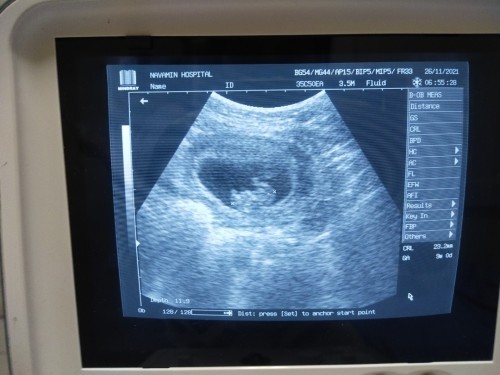

วันนี้ไปฝากครรภ์มาค่ะ คุณหมออัลตร้าซาวด์ แจ้งว่า9weekแล้ว แต่เขียนในสมุดมาว่าไม่ได้ยินเสียงหัวใจน้อง นัดอีกทีปลายเดือนธันวา ทำไงดีคะ ตอนนี้เครียดมากเนื่องจากเป็นท้องแรกค่ะ 😥